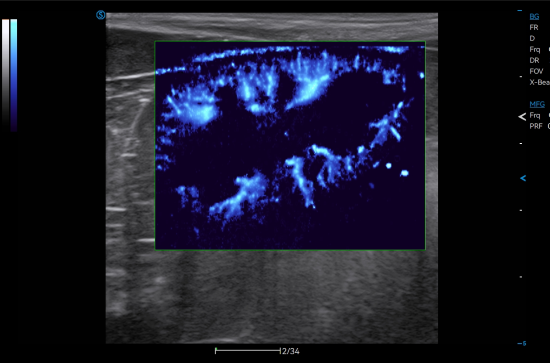

● Micro Flow captures micro blood flow signals to precisely reflect the blood flow perfusion status in organs.